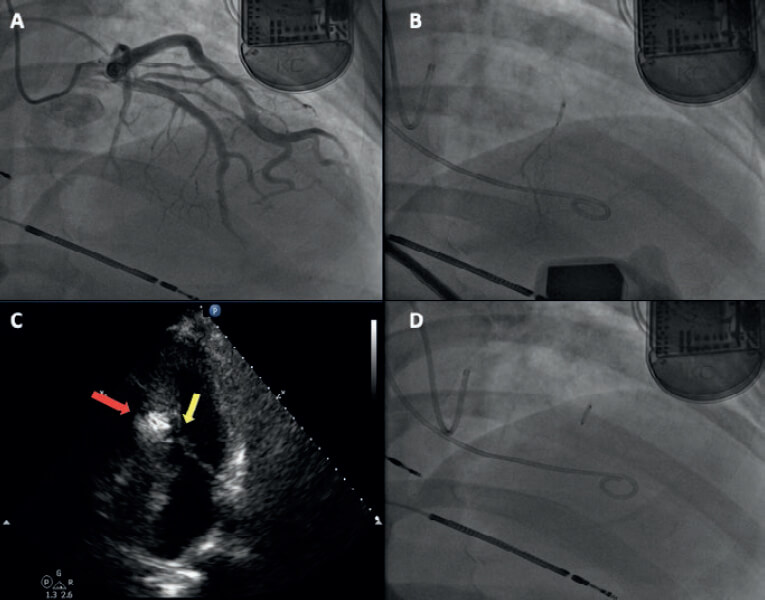

Se decidió realizar una ablación septal con alcohol de rescate, en la que se registró un gradiente intraventricular de 65 mmHg y tras la extrasistolia de 110 mmHg; se realizó una inyección de contraste burbujeado para elegir la rama septal objetivo (figura 3) y una inyección de 0,1 ml de alcohol por cada milímetro de septo contrastado. En la ecocardiografía se midió un septo contrastado de 23 mm y se administraron 2,3 ml de alcohol en la segunda rama septal.

Figura 3. A: coronariografía. B: inyección de contraste burbujeado en la segunda rama septal. C: contrastación de la zona septal susceptible (flecha). D: balón over the wire a través del cual se administró el alcohol.